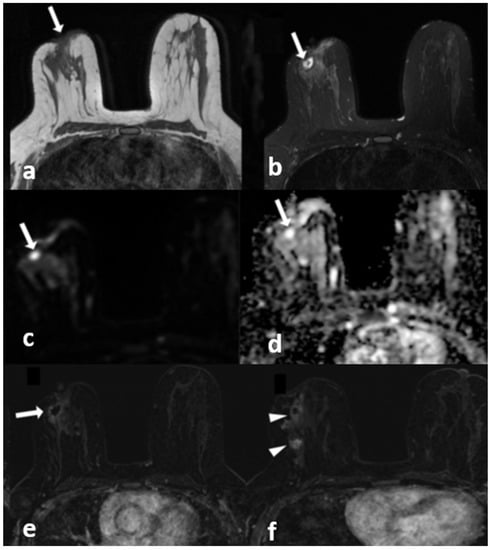

Figure 4.

A 40-year-old woman with histopathologically proven idiopathic granulomatous mastitis involving the left breast. (a) T1-weighted fast spin echo axial MR image of the patient shows mild parenchymal asymmetry in the upper outer quadrant of the left breast (star). (b) Axial fat-saturated T2-wieghted fast spin echo MR image, corresponding to (a), which reveals a moderate signal increase in the parencyma (star). (c) Axial contrast-enhanced subtracted image demonstrates a heterogeneous enhancement in the parenchyma (arrows) and a pathologic enhancement extending to the skin in the periareolar region (arrowhead). (d) ADC map at the same location shows a moderate signal decrease (stars) revealing restriction of diffusion in the area corresponding to (a–c).

Figure 6.

A 42-year-old woman with histopathologically proven invasive ductal carcinoma involving the right breast. (a) T1-weighted fast spin echo axial MR image of the patient shows parenchymal asymmetry in the retroareolar region along with nipple retraction (arrow). (b) Axial fat-saturated T2-weighted fast spin echo MR image, corresponding to (a), which reveals a cystic lesion (arrow) with a moderate signal increase in the parenchyma. (c) Diffusion-weighted and (d) ADC map show that the cystic lesion had no restriction of diffusion (arrows). (e) Contrast-enhanced subtracted image demonstrates a slight thin wall enhancement around the cystic lesion (arrow); (f) following the inferior image to (e) shows similar contiguous lesions demonstrating peripheral slight enhancement in the adjacent parenchyma (arrowheads).